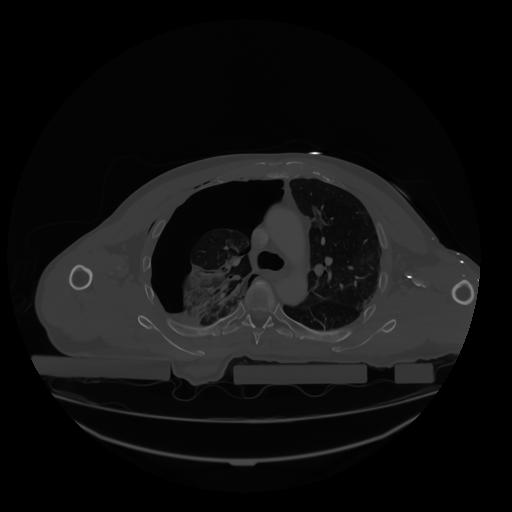

28 CUERPO,CE,Vol,2.0,CUERPO,,